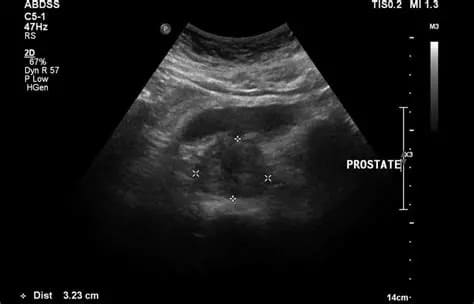

Endoanal Ultrasonography is a specialized imaging test used to evaluate the anal canal and surrounding structures using a high-resolution ultrasound probe inserted into the rectum. It helps detect fistulas, abscesses, sphincter damage, and other anorectal conditions.

4. Images of anal canal, sphincter muscles, and fistula tracts are recorded